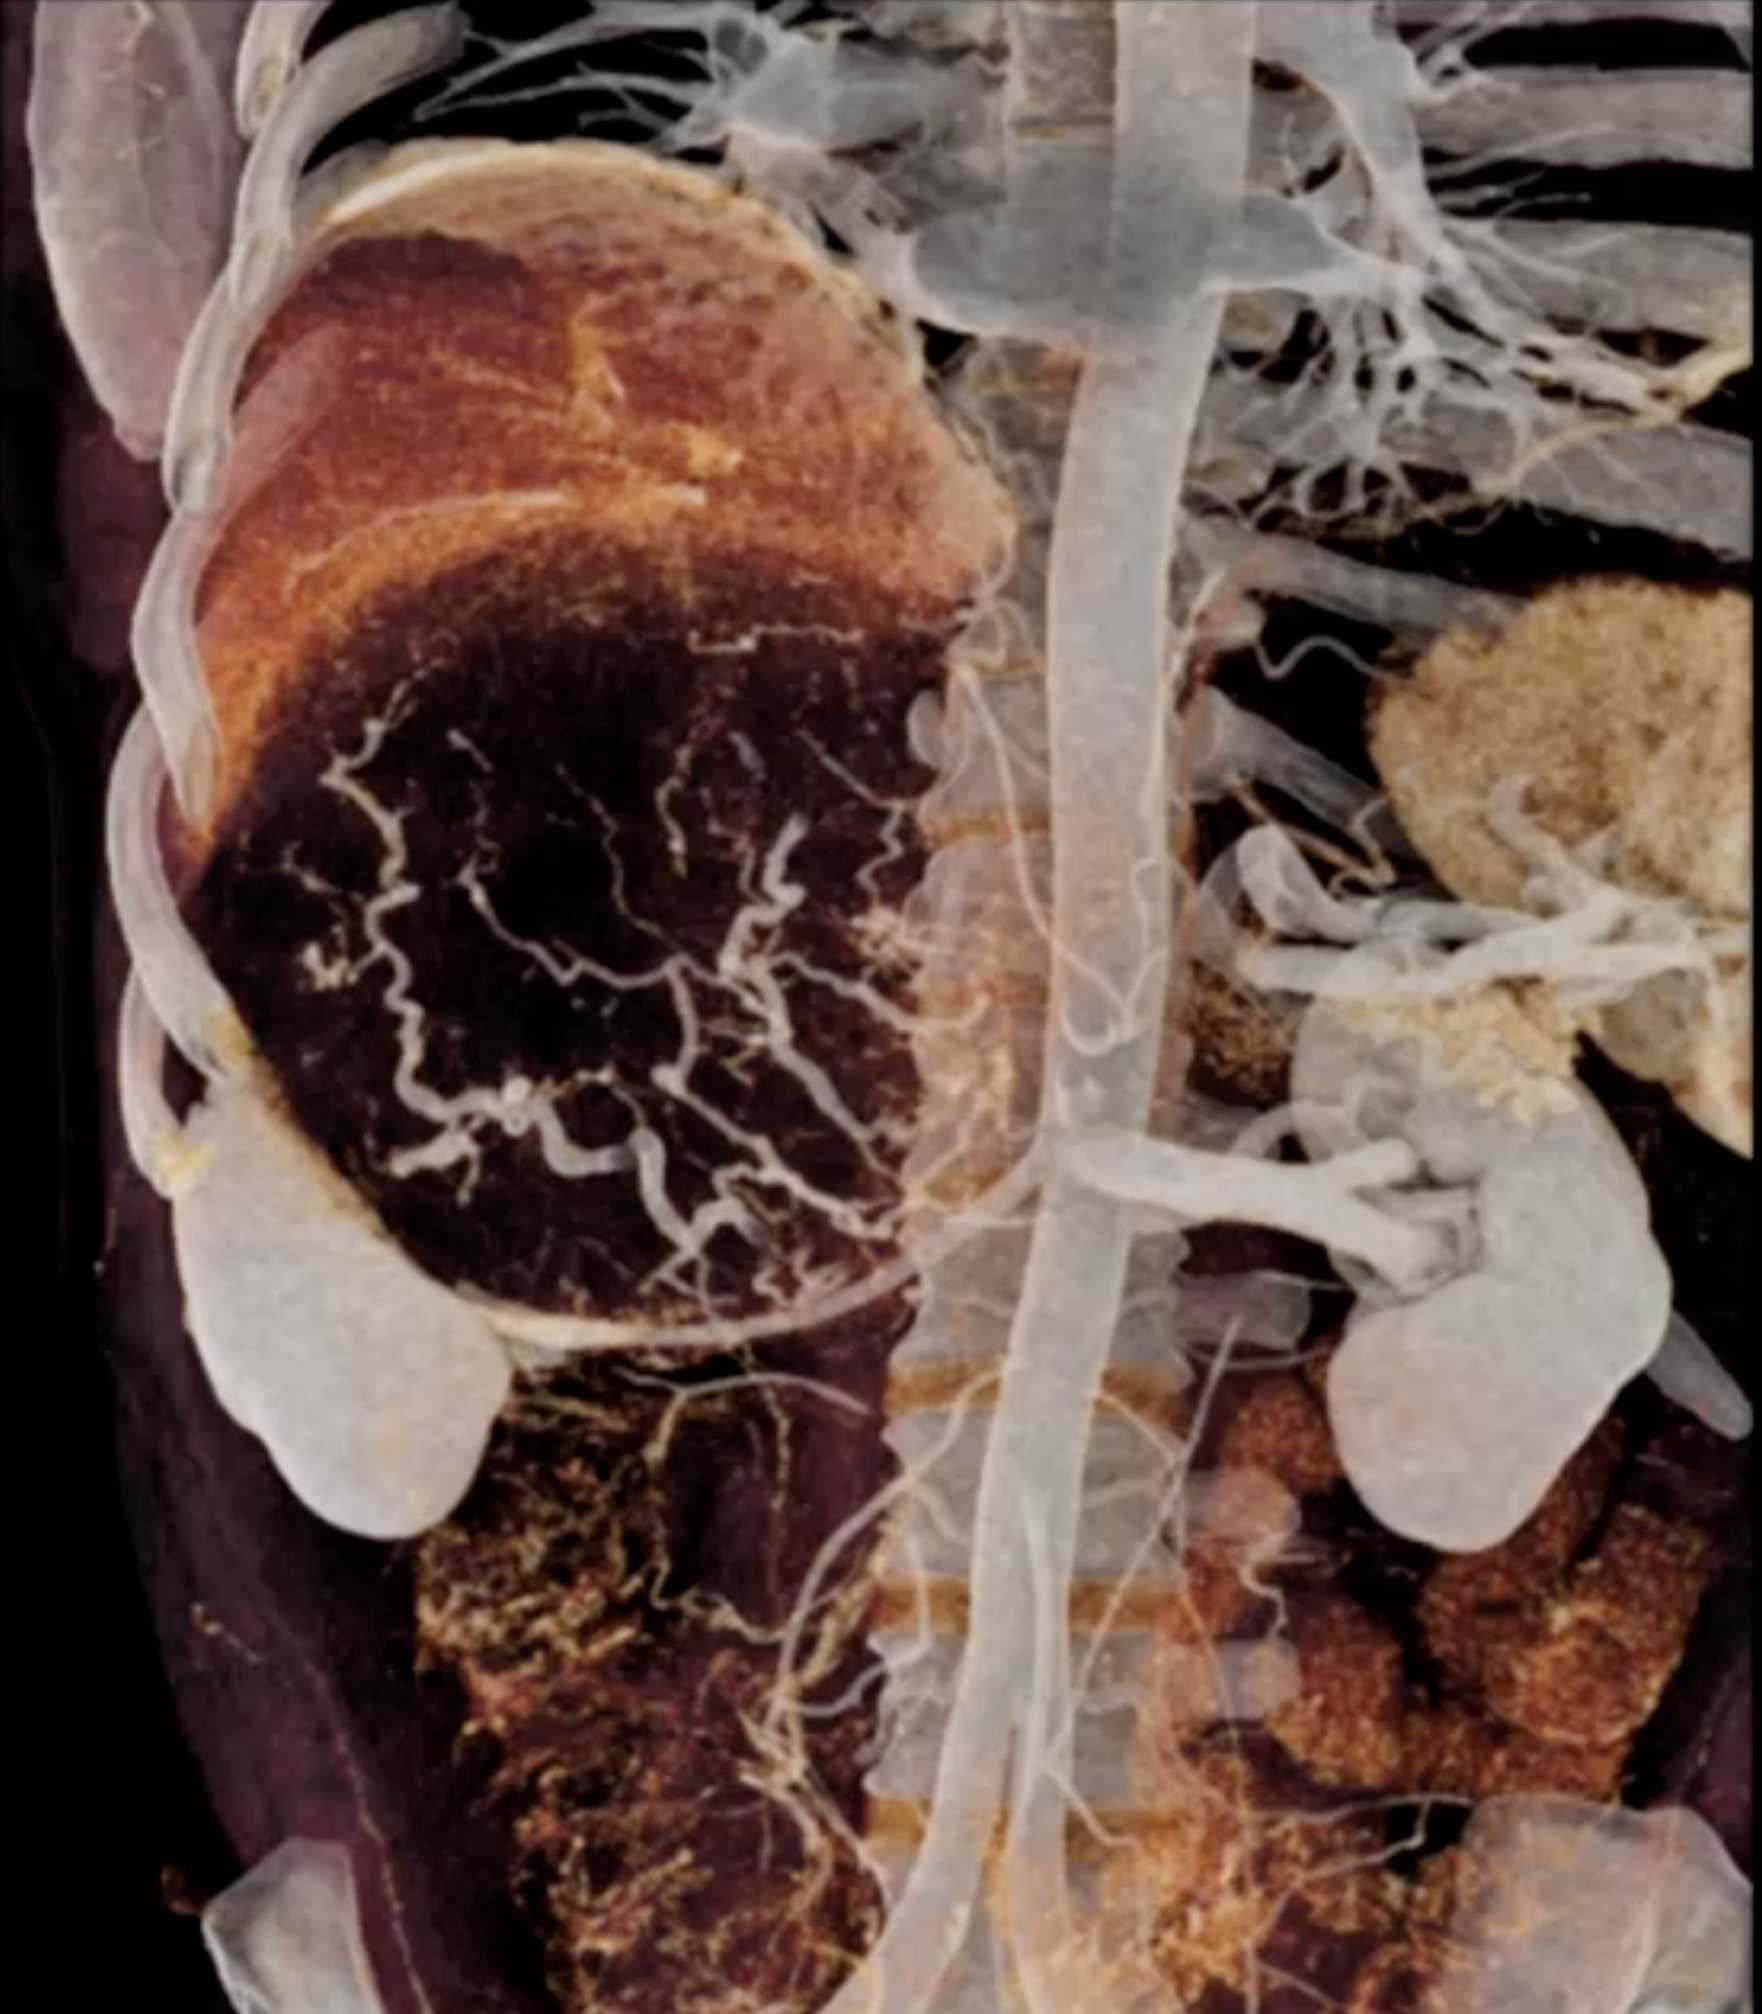

Left Adrenal Metastases from Renal Cell Carcinoma